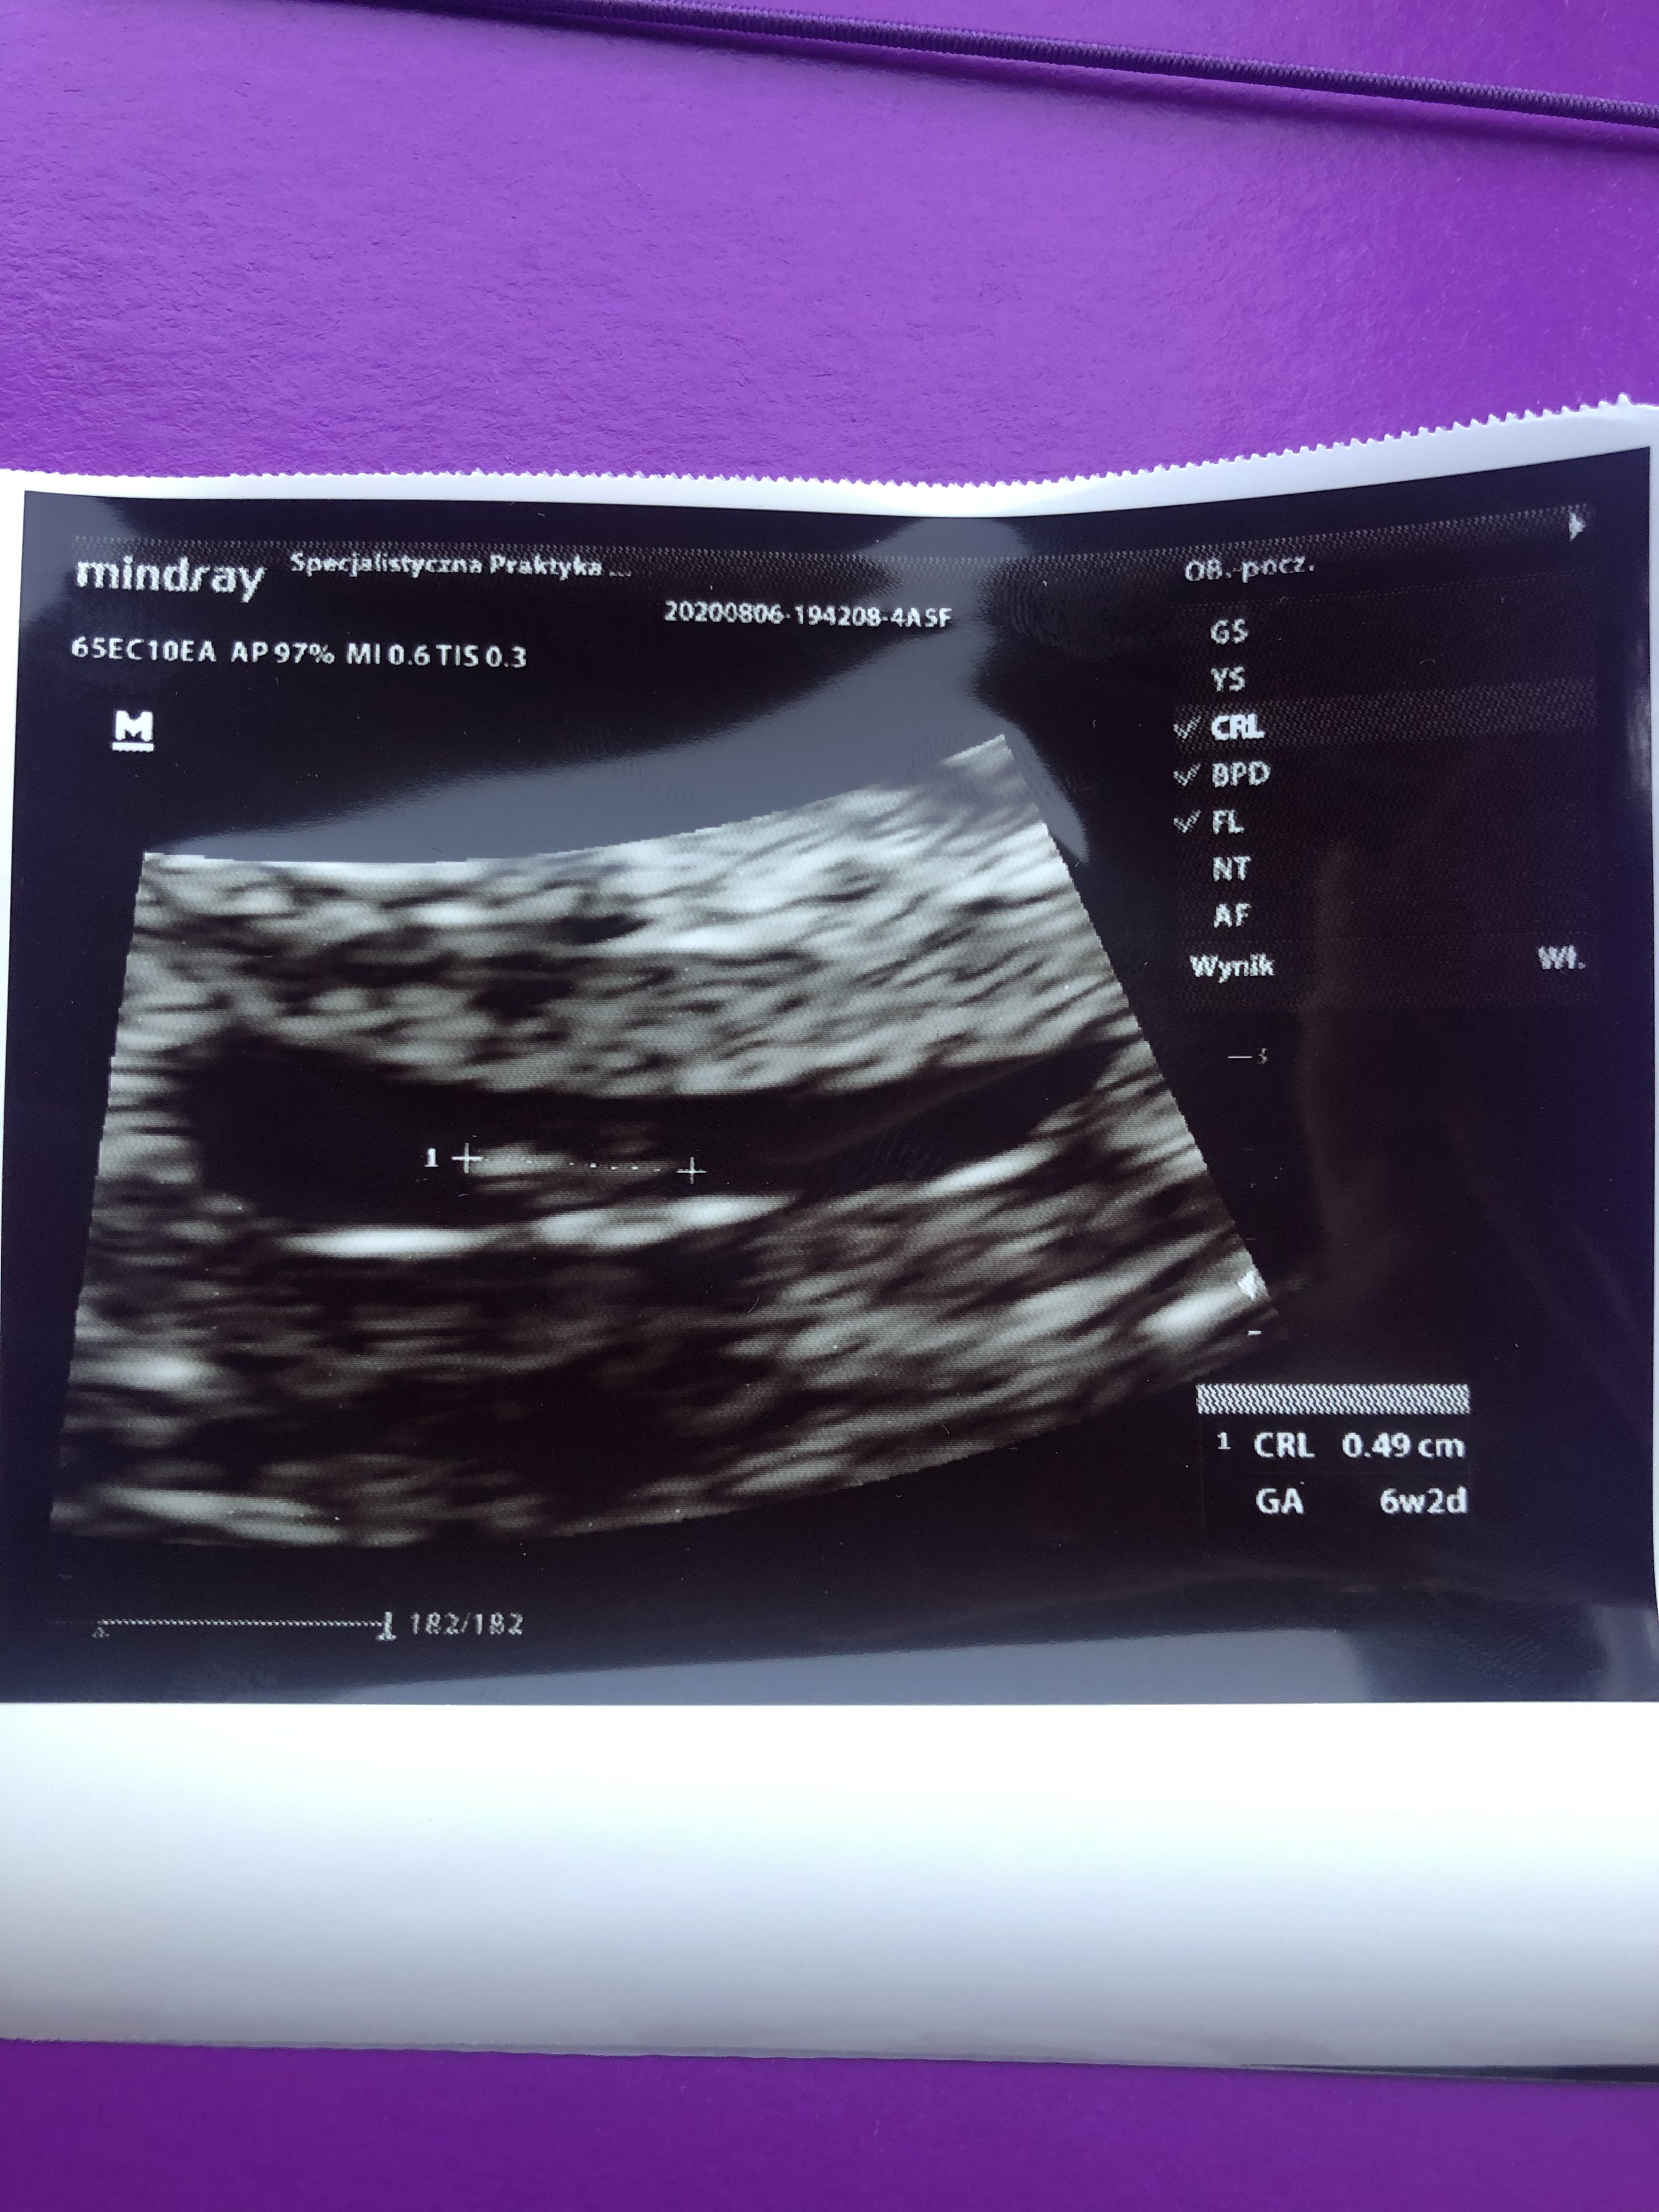

Hej dziewczynki, u mnie dziś pierwsza wizyta u ginekologa, aktualnie jestem 6+6 😍 a poziomeczka 🍓 ma 0,50 cm i bijące serduszko 💖 Według lekarza termin porodu 26.03.2021, a według aplikacji przez dłuższe cykle 01.04.2021, zobaczymy kiedy maleństwo wyjdzie na swiat, od samego początku jestem na kwietniowych mamach, ale tutaj tez chciałam się pochwalic 😍